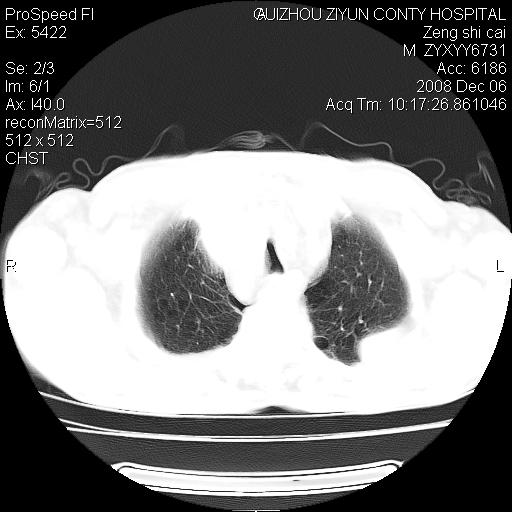

标题: CT16961:M、71岁,咳嗽半年,无血痰;胸片示右肺占位。 [打印本页]

标题: CT16961:M、71岁,咳嗽半年,无血痰;胸片示右肺占位。

1)考虑右肺上叶纵隔型肺癌伴纵隔淋巴结转移。2)心包积液,双侧胸腔积液。

右肺上叶纵隔型肺癌伴纵隔淋巴结转移。心包积液,双侧胸腔积液。